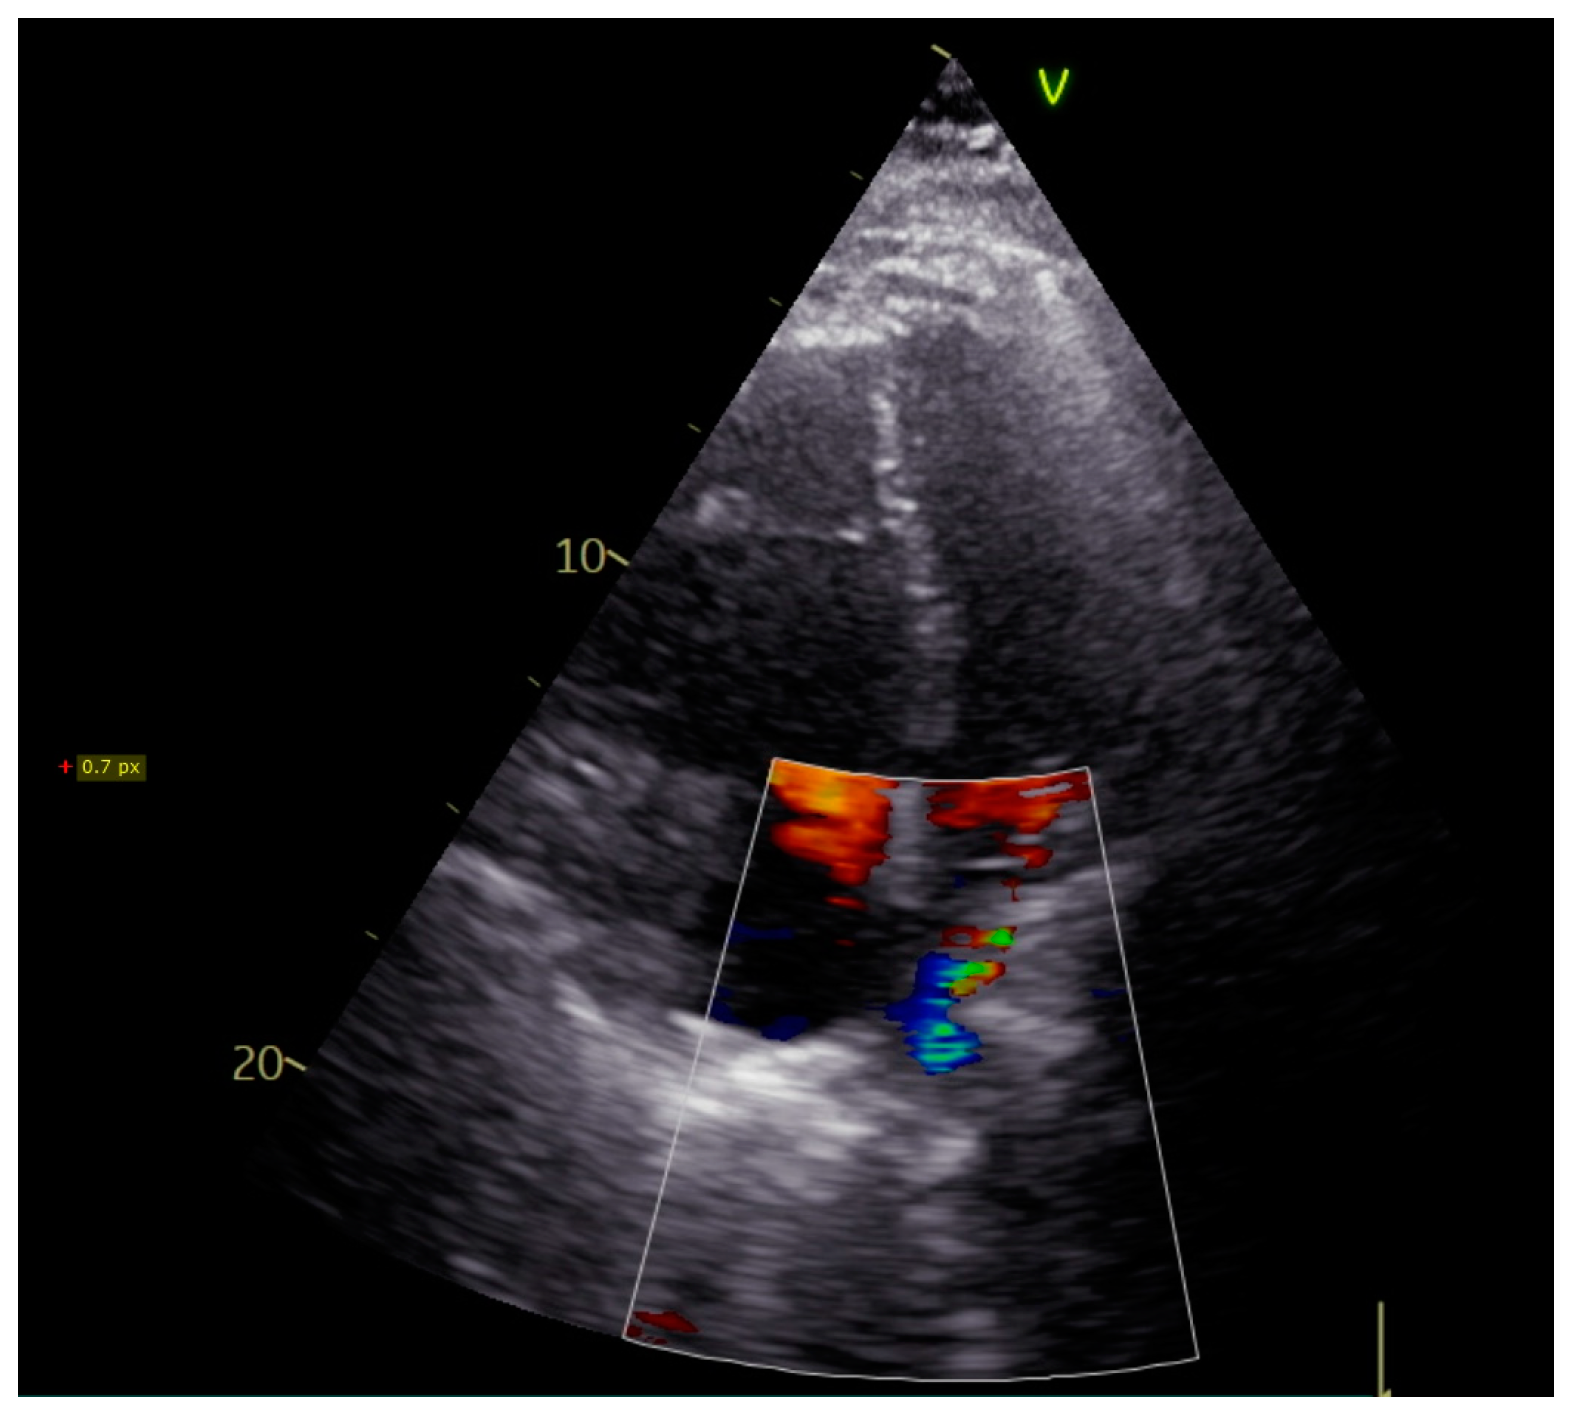

Upon admission, the patient was in sinus rhythm with no atrial fibrillation episodes at Holter monitorization. Transthoracic echocardiography showed moderate dilation of right heart cavities, severe pulmonary hypertension (70 mmHg), and a turbulent flow in superior pulmonary veins (Figure 1). Pneumological evaluation revealed a mild restrictive dysfunction with a blood oxygen level of 95%. As the patient was under treatment with Eliquis® (apixaban), pulmonary embolism was not suspected. Given his history of radiofrequency ablation for atrial fibrillation, the cardiologist scheduled the patient for a cardiac CT angiography to exclude a post-procedural stenosis of the pulmonary veins.

Figure 1.

Transthoracic echocardiography showing turbulent flow in the distal part of the right superior pulmonary vein.